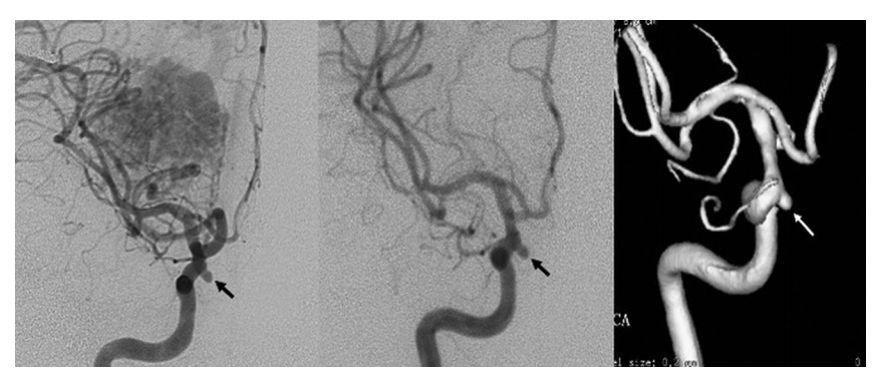

病例一:左图显示该患者为右侧顶枕叶AVM,右侧床突旁颈内动脉处存在小的血流相关动脉瘤(箭头)。中图及右图提示立体定向 γ 刀手术后 54 个月的常规血管造影显示 BAVM 几乎完全闭塞,但是近端 FA 没有明显的形态变化。